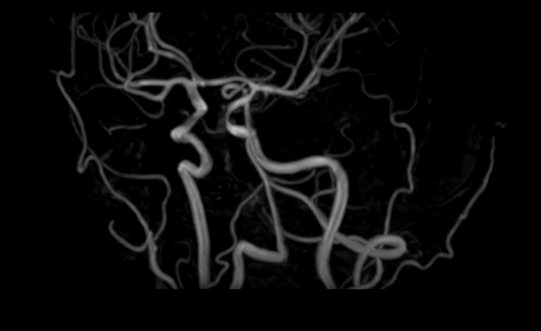

Исследования выполняются на современном высокопольном томографе экспертного класса TOSHIBA VANTAGE TITAN 1,5 Тесла, который использует разные режимы сканирования с толщиной среза от 1мм в различных плоскостях с последующей цифровой обработкой полученных данных для создания трехмерных изображений. МР-ангиография отображает состояние артериальной системы кровоснабжения головного мозга. МР-венография головного мозга позволяет детально изучить особенности венозного русла головного мозга.

Компьютерная программа обрабатывает данные, полученные при сканировании, и формирует объемные изображения как самого мозга, так и сосудистой системы в отдельности без прилегающих тканей. Методики применяются одновременно и взаимодополняют друг друга.

• патология нервов на фоне сосудистых проблем (вазоневральный конфликт — сдавление нерва близлежащим сосудом, также на фоне патологической извитости, аневризмы, сосудистой мальформации).